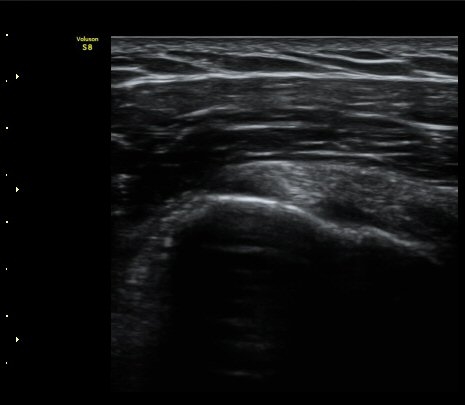

°ß°©ÇÏ±Ù°Ç Á¾´Ü¸é°Ë»ç¿¡¼­ ƯÀÌ ¼Ò°ß ¾øÀ½

(no specific abnormal findngs with longitudinal scan of subscapularis tendon) »çÁø 3